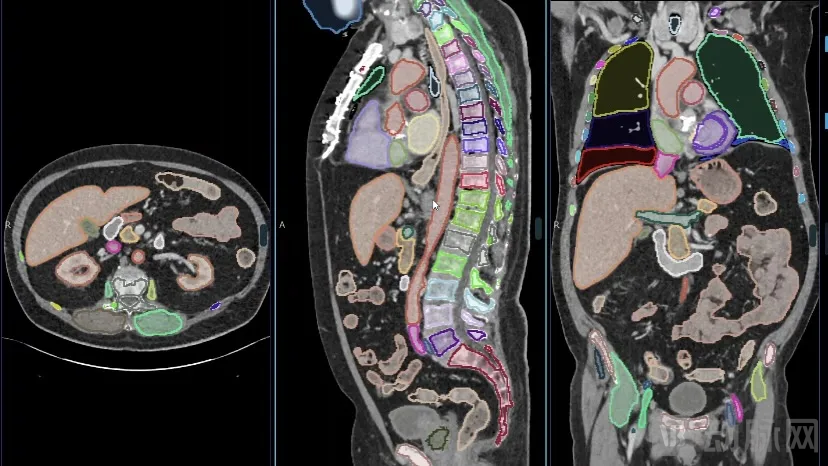

NVIDIA 一直专注于研究 3D CT 分割,并在最近开发出了 VISTA-3D(多功能图像分割和注释)。该模型在超过 12,000 个数据卷上系统训练而成,这些数据卷涵盖了 127 种人体解剖结构和各种病变(包括肺结节、肝肿瘤、胰腺肿瘤、结肠肿瘤、骨病变和肾肿瘤)。

该模型提供了精准的框外分割与最先进的零样本交互式分割。这一新型模型设计和训练策略为开发多功能医学图像基础模型带来了希望。

分割全身:实现全身探索,这对于了解影响多个器官的复杂疾病和制定整体治疗计划至关重要。

在 Healthcare 下找到 VISTA-3D,并使用示例数据对其进行测试。以轴向和冠状或矢状视图查看测试数据集。VISTA-3D 可以分割 100 多个器官,您也可以选择感兴趣的特定类别。